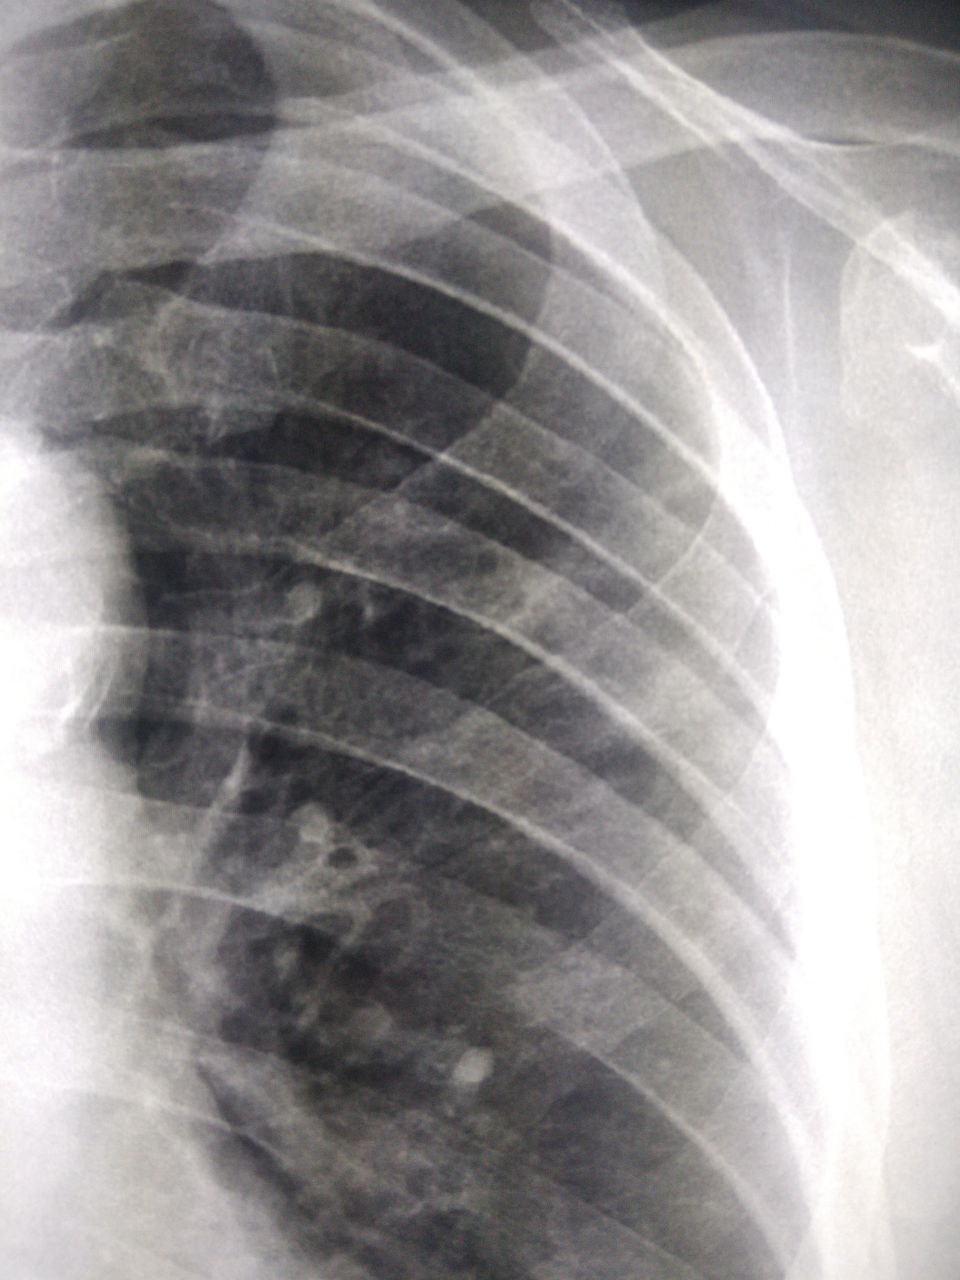

Срочно, кто разбирается в детских снимках? Ни анамнеза, ни архива, только снимки и направление

NL

Здравствуйте. Анамнез. Клиника

NL

Срочно, кто разбирается в детских снимках? Ни анамнеза, ни архива, только снимки и направление